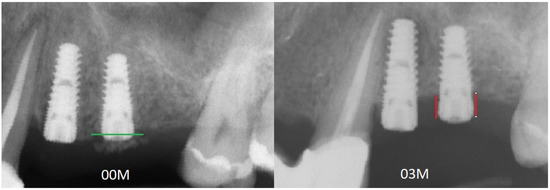

Figure 6.

Figure presenting two radiographs. On the left is the radiograph image taken immediately after dental implant placement at 00M. The level of the bone at the beginning of the observation is marked by a green line. On the right is the RTG at 3 months of observation after implant placement. The red lines mark the marginal bone loss in relation to the previous bone level. Abbreviations: RTG—radiograph image; 00M—0 months of observation.